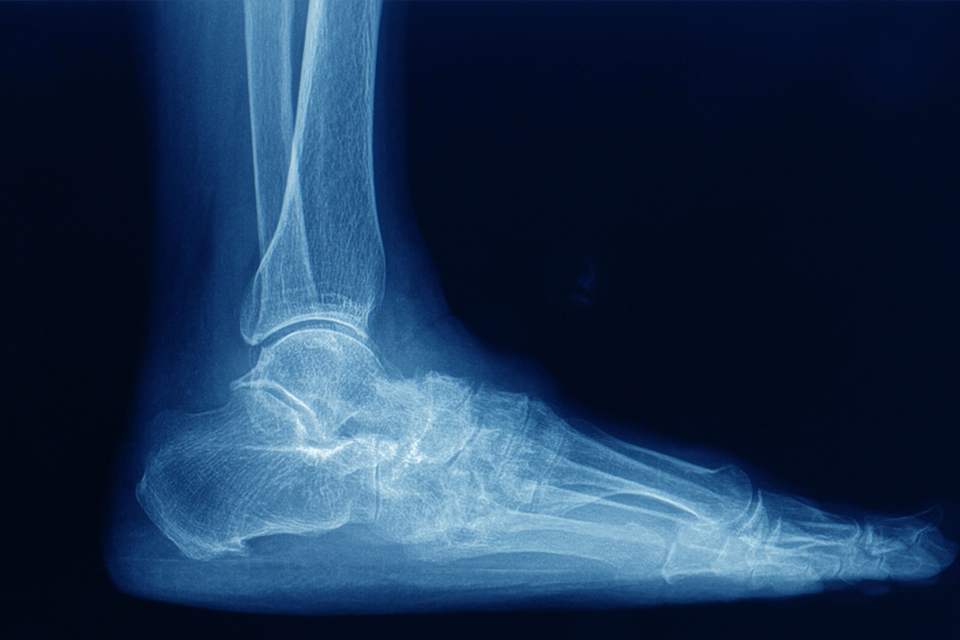

Diagnostic Approach at Stepsmartortho

At Stepsmartortho, we employ a comprehensive diagnostic approach guided by Dr. Santhosh C Reddy, integrating detailed clinical examination, gait analysis, and advanced imaging when necessary. Early-stage arthritis may not always appear prominently on standard X-rays, making expert clinical judgment essential.

Foot deformity X-Ray

Accurate diagnosis ensures that treatment strategies are appropriately tailored to disease stage and individual patient needs.